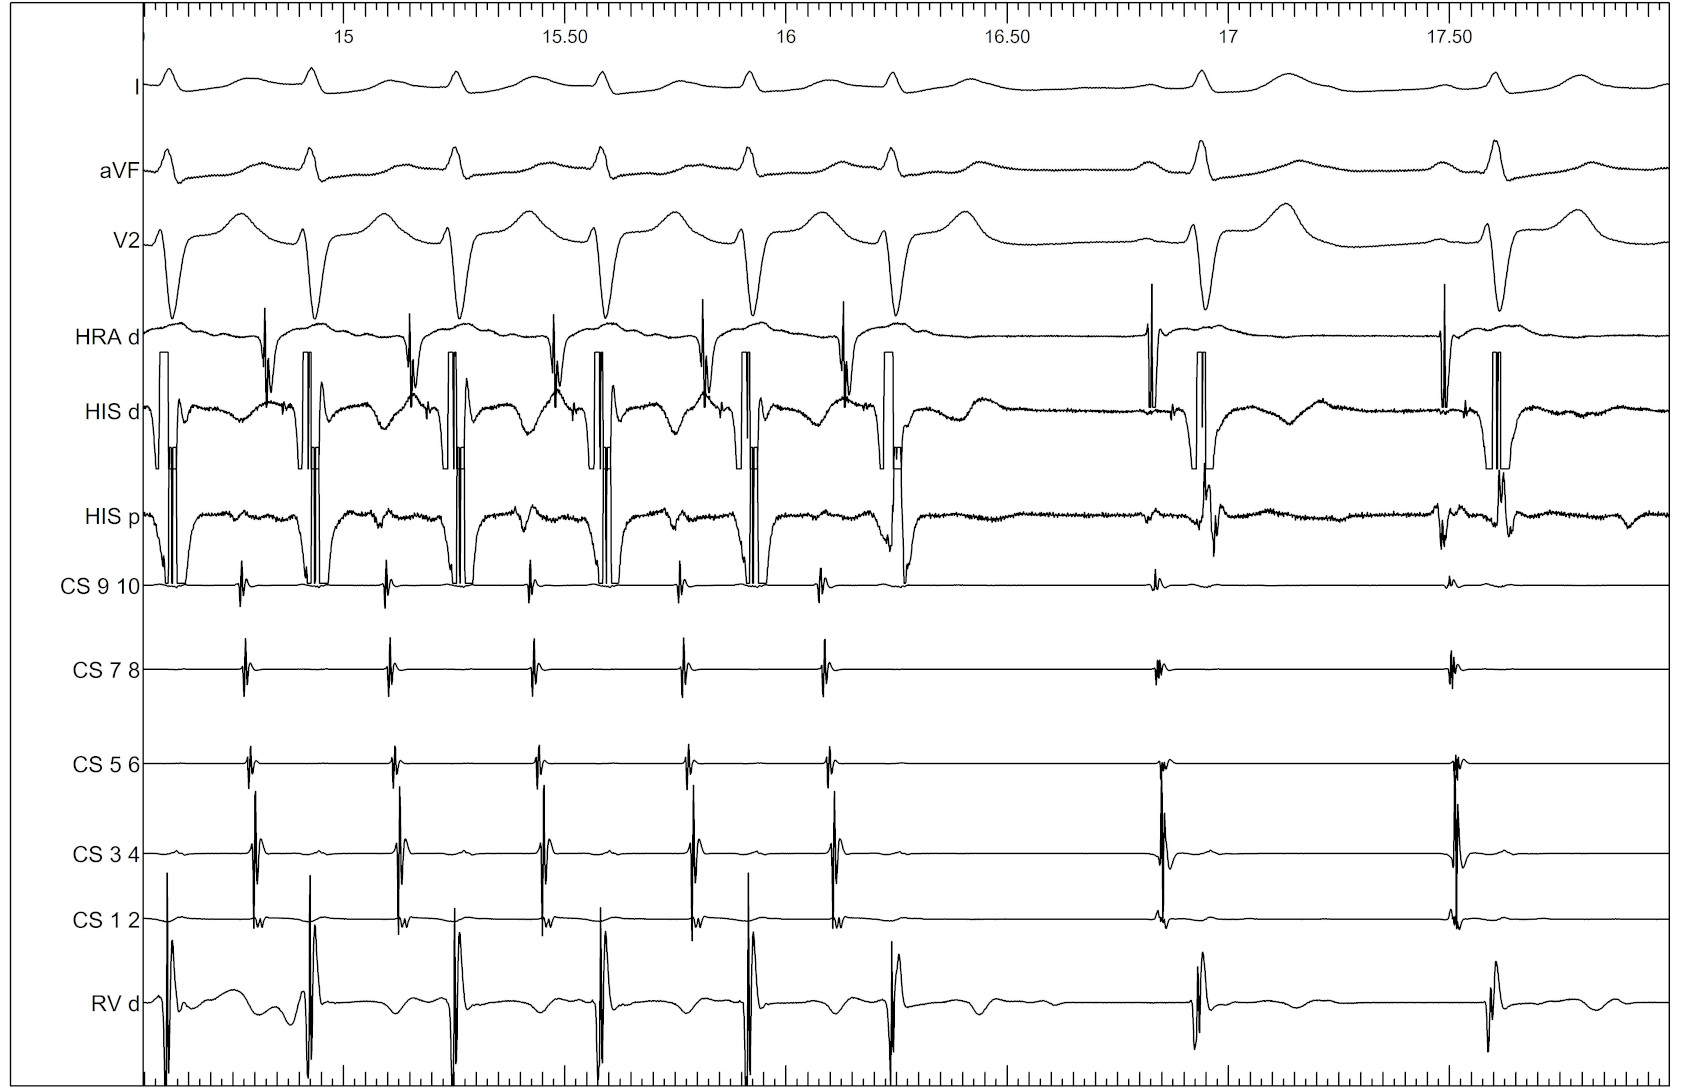

Stepwise approach

• Was the atrium entrained ?

• Which is the last entrained A ?

• What is the return response - VAV vs VAAV

• What is the cPPI-TCL ? (VAV)

• What is the SA-VA (VAV)

Tachycardia continues

vav_avnrt.jpg